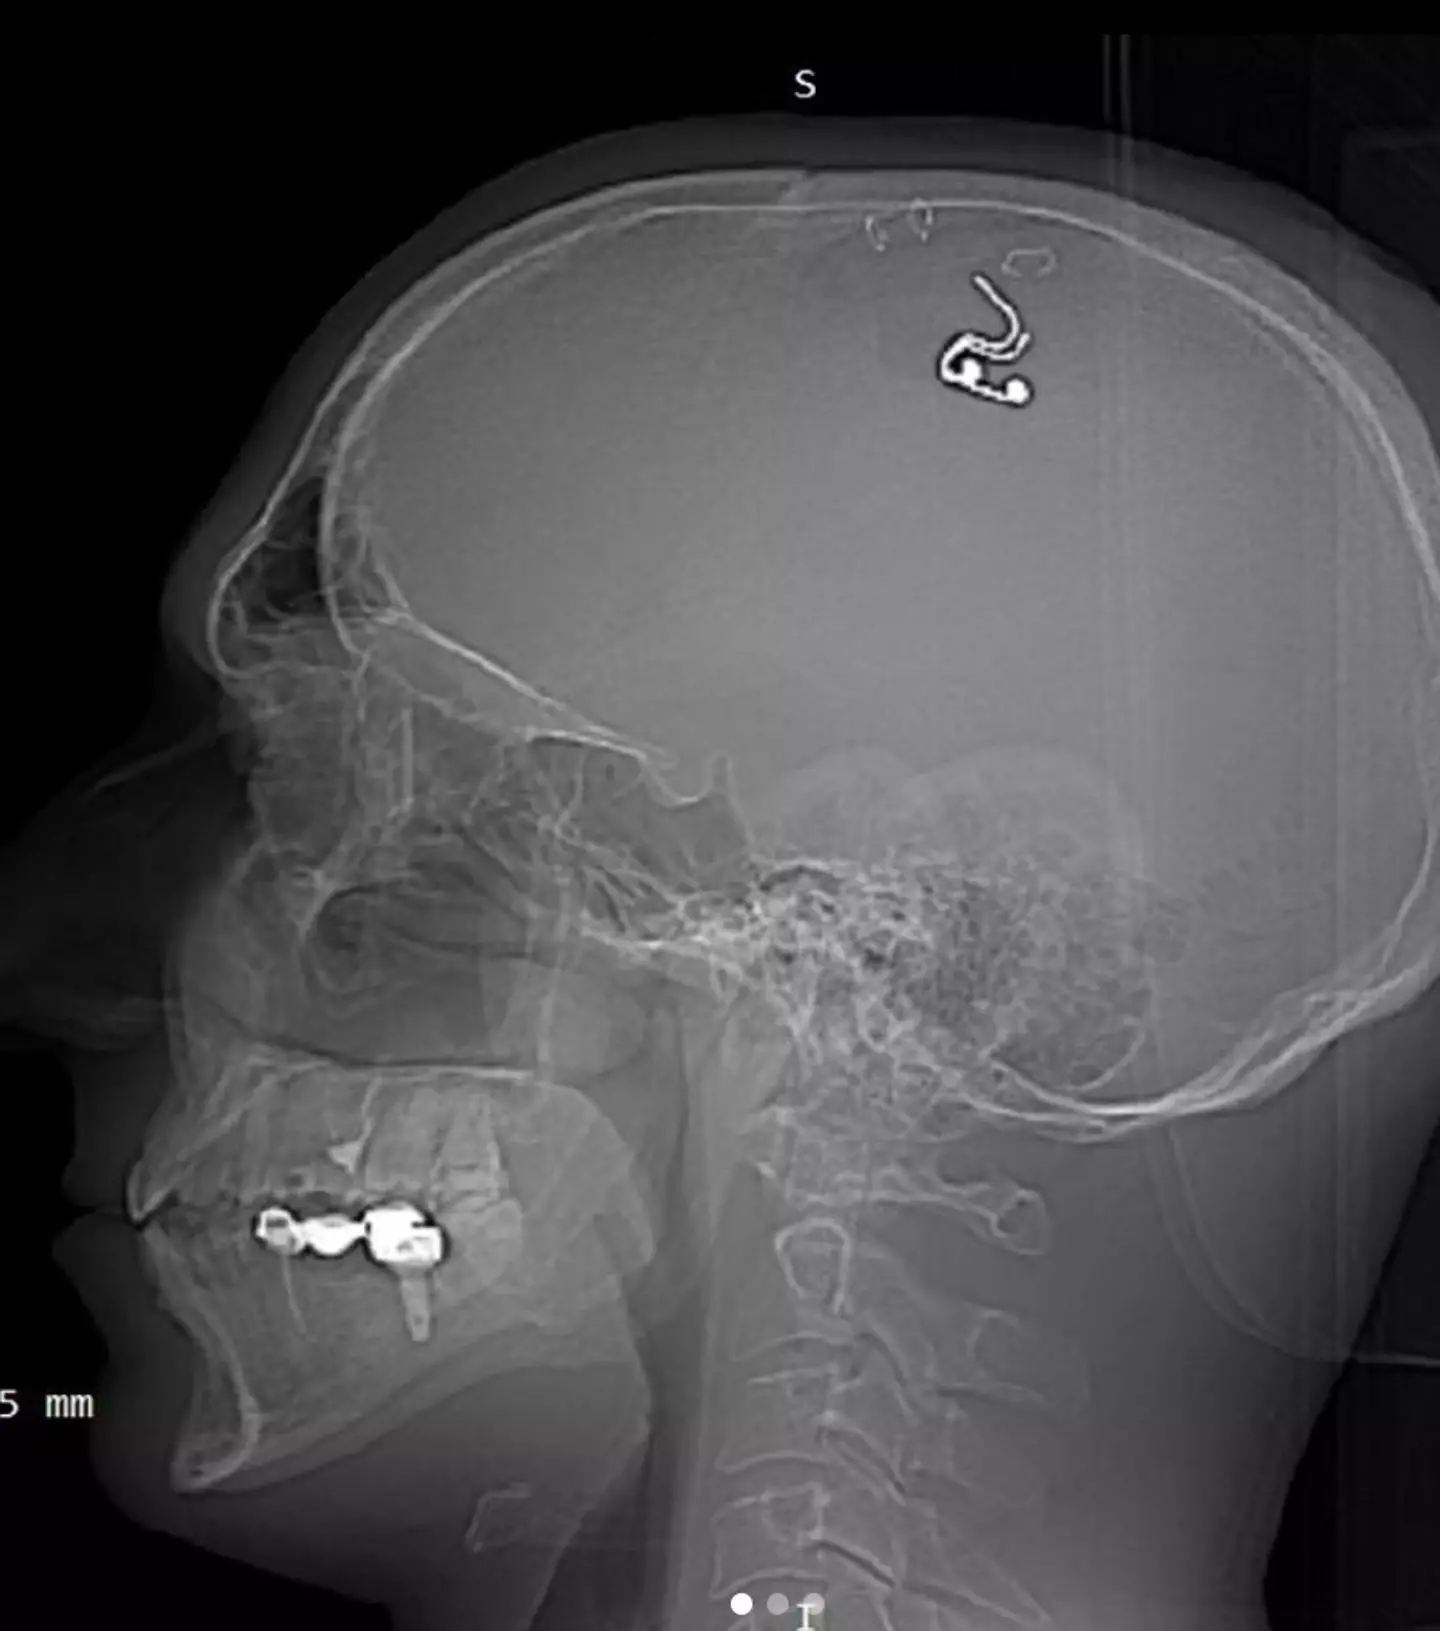

A man claims he has implanted a chip into his brain in the hopes that he will one day be able to control his own dreams.

Russian Michael Raduga lost ‘a lot of blood’ during his 10-hour DIY neurosurgery, which he performed at his home last month.

Despite opting to operate on his own brain, Raduga told the Daily Mail he has no neurosurgery qualifications and that he held parts of his skin back with paper clips while going at his skull with a drill he found in a hardware store so he can implant the electrode.

Five weeks after implanting the chip, Raduga removed it but there are concerns that he could already be at risk of long-lasting damage due to carrying out the procedure.